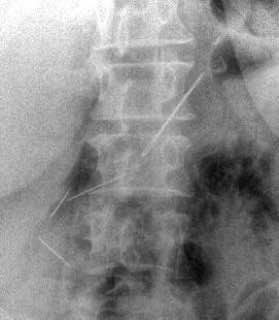

В Красногорске 59-летняя пациентка обратилась в больницу с болями. Обследование показало, что в её брюшной полости находятся четыре швейные иглы — женщина проглотила их около месяца назад.

Пришлось делать полостную операцию. Все четыре предмета успешно извлекли, один из них даже проник в поджелудочную железу — орган удалось сохранить.